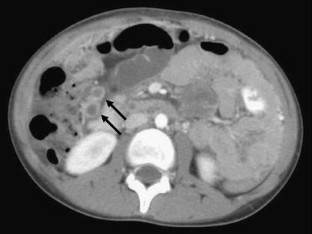

Fig. 1